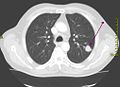

CT-Thoraxaufnahme (axiales Schnittbild) -